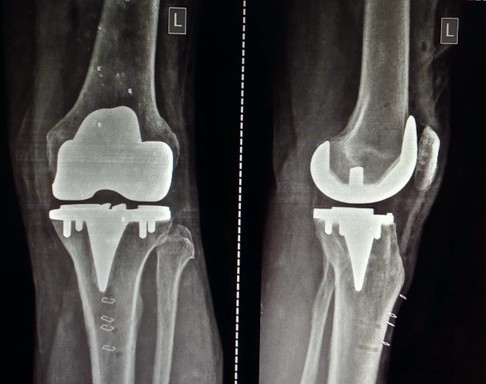

Figure 2: Post-operative x-ray. Intra-operative stressed laxity and limb alignment, and post-operative stressed laxities and limb alignment were assessed.